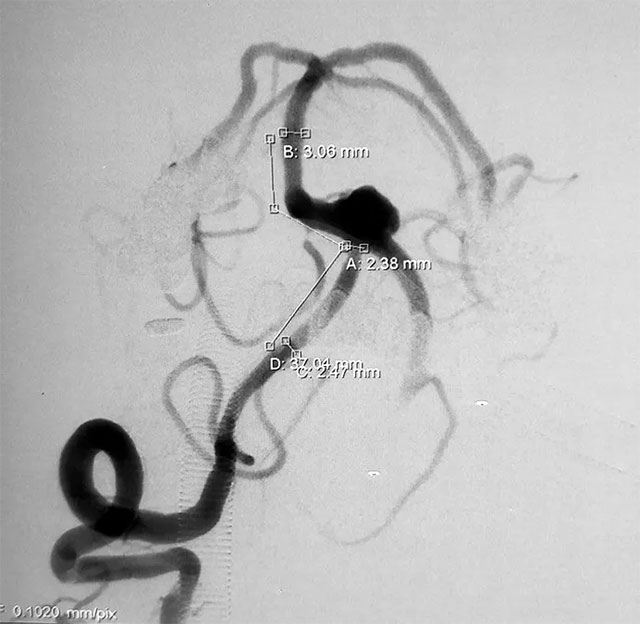

▲ 术前造影

头颅CTA显示:左椎动脉多发狭窄及钙化,呈串珠样改变,椎基底动脉夹层动脉瘤,可见数枚水泡样动脉瘤。患者既往有高血压病史10余年,两月前有“头部外伤史”。血压检查,收缩压153毫米汞柱,舒张压80毫米汞柱,神志清醒,口角右歪。

张琪博士指出,该患者所患颅内夹层动脉瘤影像上属于经典型(I型),且动脉瘤已破裂出现急性蛛网膜下腔出血,导致头晕、头痛、恶心等症状,病情凶险,再出血的风险极大,应及时手术治疗。

普通动脉瘤,载瘤动脉壁是完整的,形态也是规则的,对于这种宽颈动脉瘤放支架相对容易,而夹层动脉瘤其载瘤动脉本身就是多发斑块和狭窄,稍有不慎导丝进入夹层,容易把血管内膜撕裂,导致血管闭塞。针对普通动脉瘤一般是先填弹簧圈再放支架,对于夹层动脉瘤需要先放支架解决夹层,再通过支架网孔填入弹簧圈。

并且患者血管条件非常差,DSA造影显示左侧椎动脉远端近基底动脉连接处夹层动脉瘤,伴子瘤,术中很容易破,并且左侧椎动脉闭塞,需要先进性开通,这些无疑增加了手术难度。